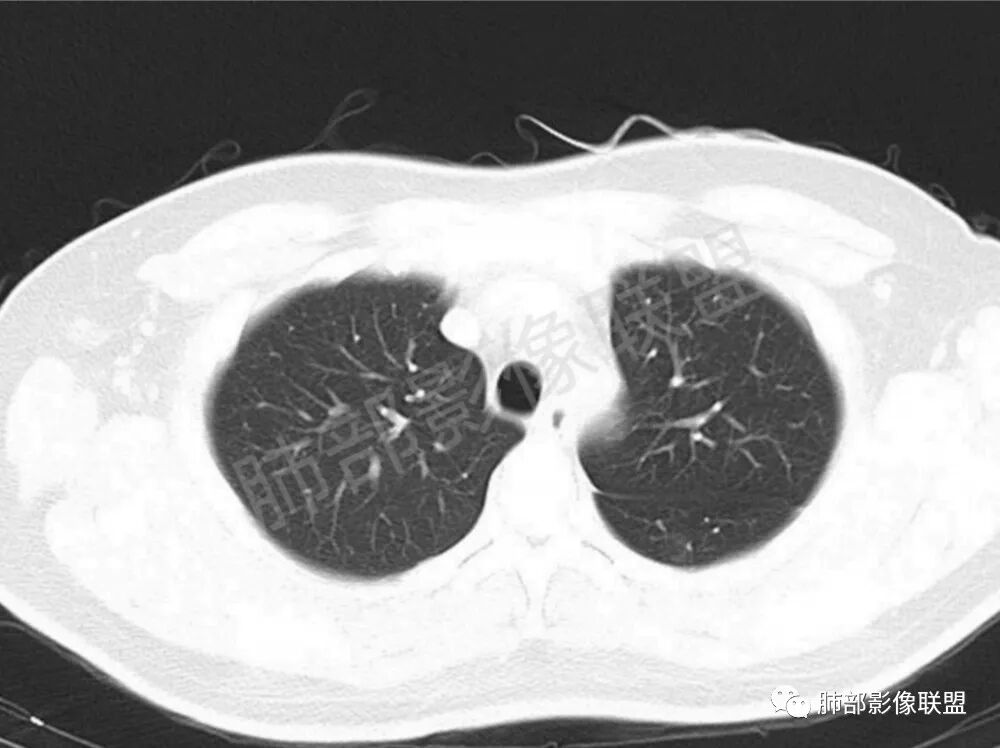

男性,22岁,HIV病史,症状半年,双肺多发大小不等结节影,边缘光滑,密度均匀,以胸膜下分布为主,部分与胸膜相连,胸膜下脂肪间隙可见,病灶近段支气管走行病灶内,远端似有堵塞,无增强图像,考虑隐球菌,鉴别:淋巴瘤,GPA

双肺多发结节影,膨隆,边缘光滑,圆顿,沿支气管血管束分布为主,部分贴胸膜,部分见空洞,空气支气管征

两肺多发结节性,大部分位于胸膜下,部分结节周围可见晕征。局部结节内可见扩张的支气管,纵隔淋巴结大,脾大,22岁男,HIV阳性,常规先考虑隐球菌。鉴别淋巴瘤,结核,马儿。

男,22,半年前咳嗽伴少痰,查HIV阳性,痰查TB阳性,既往有肺部斑片影伴空洞、纵隔淋巴结肿大、脾大。SCC、CA50、CA199、FER增高,此次胸部CT:两肺多发结节影,部分沿血管束分布,部分贴胸膜下,大小不一,密度不一,部分较散、边缘模糊,部分较实、圆钝、周围模糊晕,部分结节有支气管进入穿行自然,部分结节有血管分支自如通过。考虑HI∨相关淋巴增殖类病变,淋巴瘤?LYG?鉴别PC、TB。

1.双肺多发大小不一结节,外围为主,边界尚清,部分周围似有GGO

2.类圆形,部分与胸膜相连,糊墙

3.支气管通畅或近端堵塞

影像学缺乏特征性,以支气管血管周围、胸膜下及双肺下叶周边多发结节影最多见,结节易坏死形成空洞,伴有游走性和多变性的特征,结节周围可有磨玻璃样晕征,有时也可见单发结节影、薄壁的囊状阴影或弥漫性浸润影。肺门、纵隔淋巴结肿大少见, 可见胸腔积液和气胸。

结节型∶表现为两肺多发大小不等的结节,以两肺中下野多见,结节边缘欠锐利;